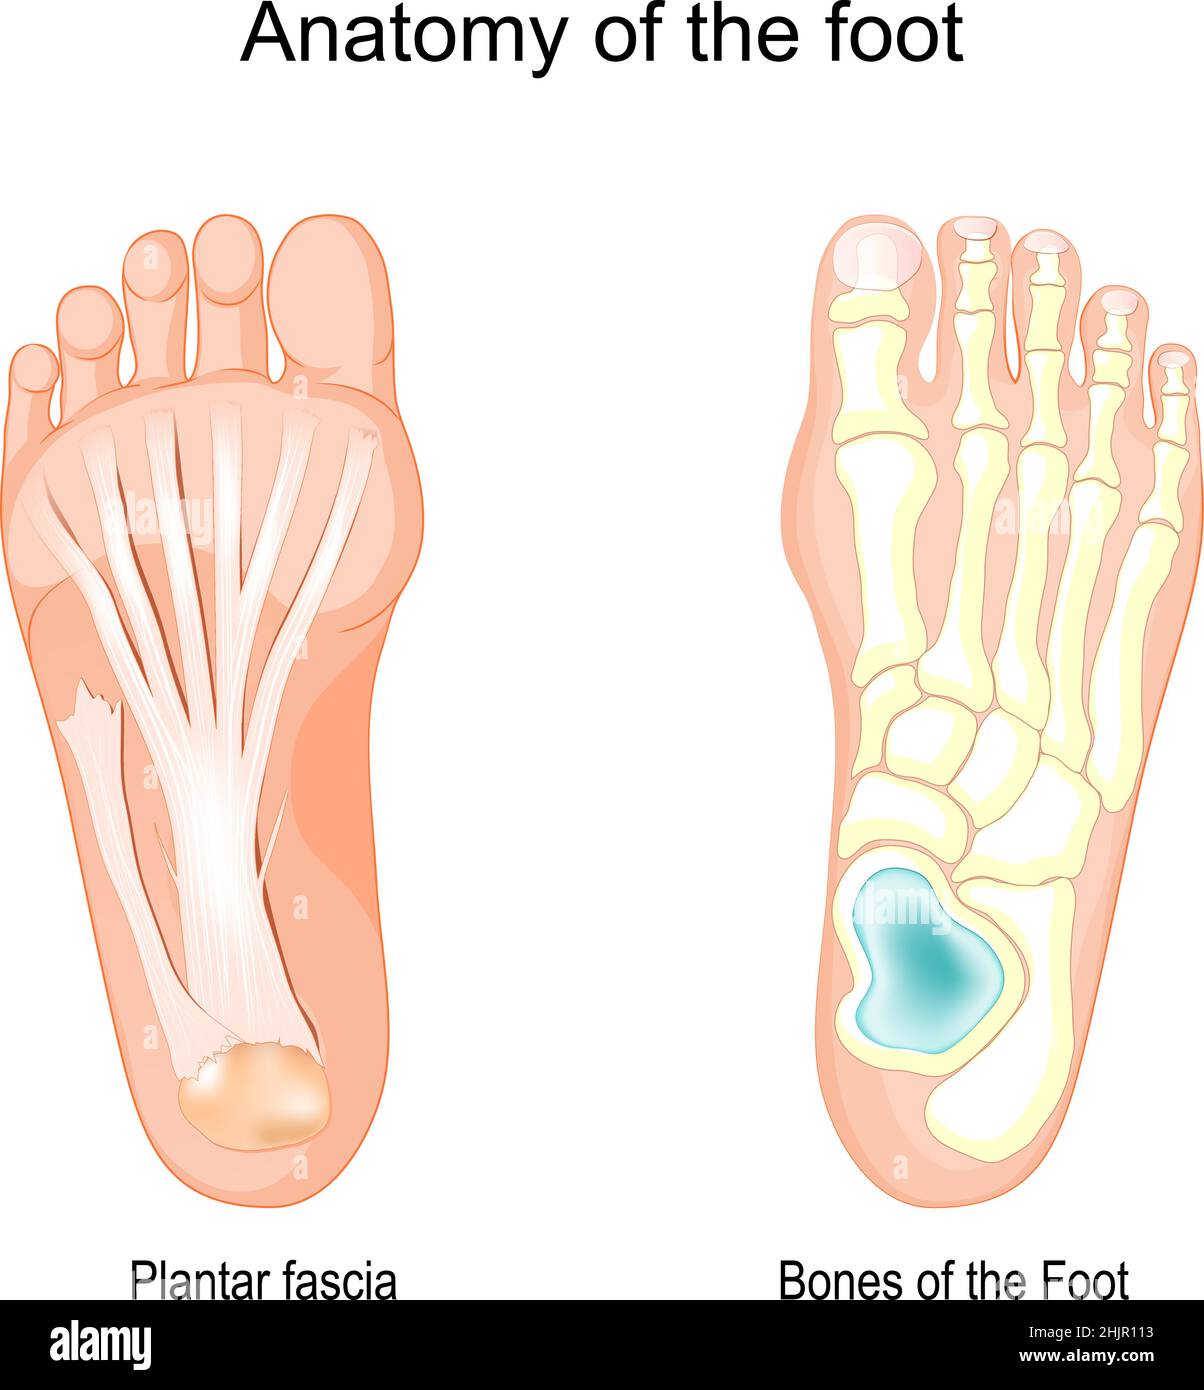

RF2J65WT4–Anatomie du pied. Pied humain avec le nom et la description de tous les os et sites. Vue de dessus et vue latérale. Arcs des pieds. Anatomie du squelette. Vecteur

RF2X200ED–L'anatomie de l'articulation de la cheville. Région talocrurale ou os sauteur. Partie du corps humain où le pied et la jambe se rencontrent. Fascia plantaire et tendon d'Achille